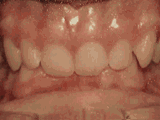

Mordida abierta:

Los dientes frontales no entran en contacto.

El paciente inició su tratamiento a la edad de 11 años y usó frenos por 26 meses. Está muy feliz con su nueva sonrisa.